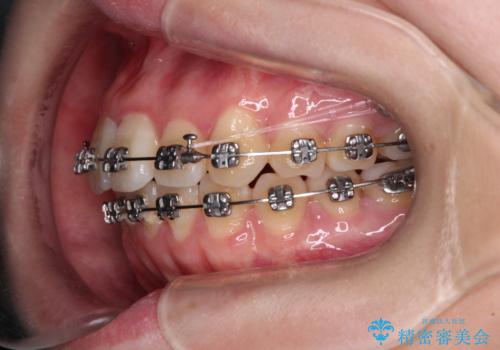

【モニター】八重歯を片側の抜歯矯正で治す メタルブラケット装置

- 八重歯とずれた正中を気にして来院された患者様です。

非抜歯矯正ではデコボコを解消することでより口元が突出する可能性があるため、上顎右右側の小臼歯1本の抜歯を行い、ワイヤー装置による矯正治療を行うこととしました。

正中位置を合わせるために、上顎臼歯部にアンカースクリューを埋入することとしました。